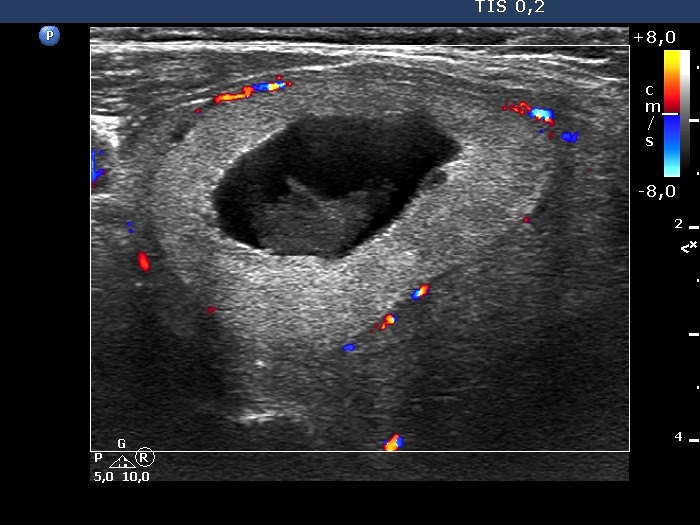

Second examination 3 years later (second row of images):

Ultrasonography. The right cystic nodule has in part refilled. Otherwise, the presentation remained unchanged.Suggestion: TSH determination in 6 months, ultrasound in 3 to 5 years.

This case illustrates how a spongiform type cyst might evolve from a central-type cystic nodule. See video and longitudinal scans of the right lobe.

The nodule has tiny hypoechoic areas, therefore the lesion can be regarded as an EU-TIRADS 4 lesion. Nevertheless, the hypoechoic areas do not raise the possibility that they would represent another pathological entity, therefore, is seems to be more accurate to classify the nodule as an EU-TIRADS 3 lesion.